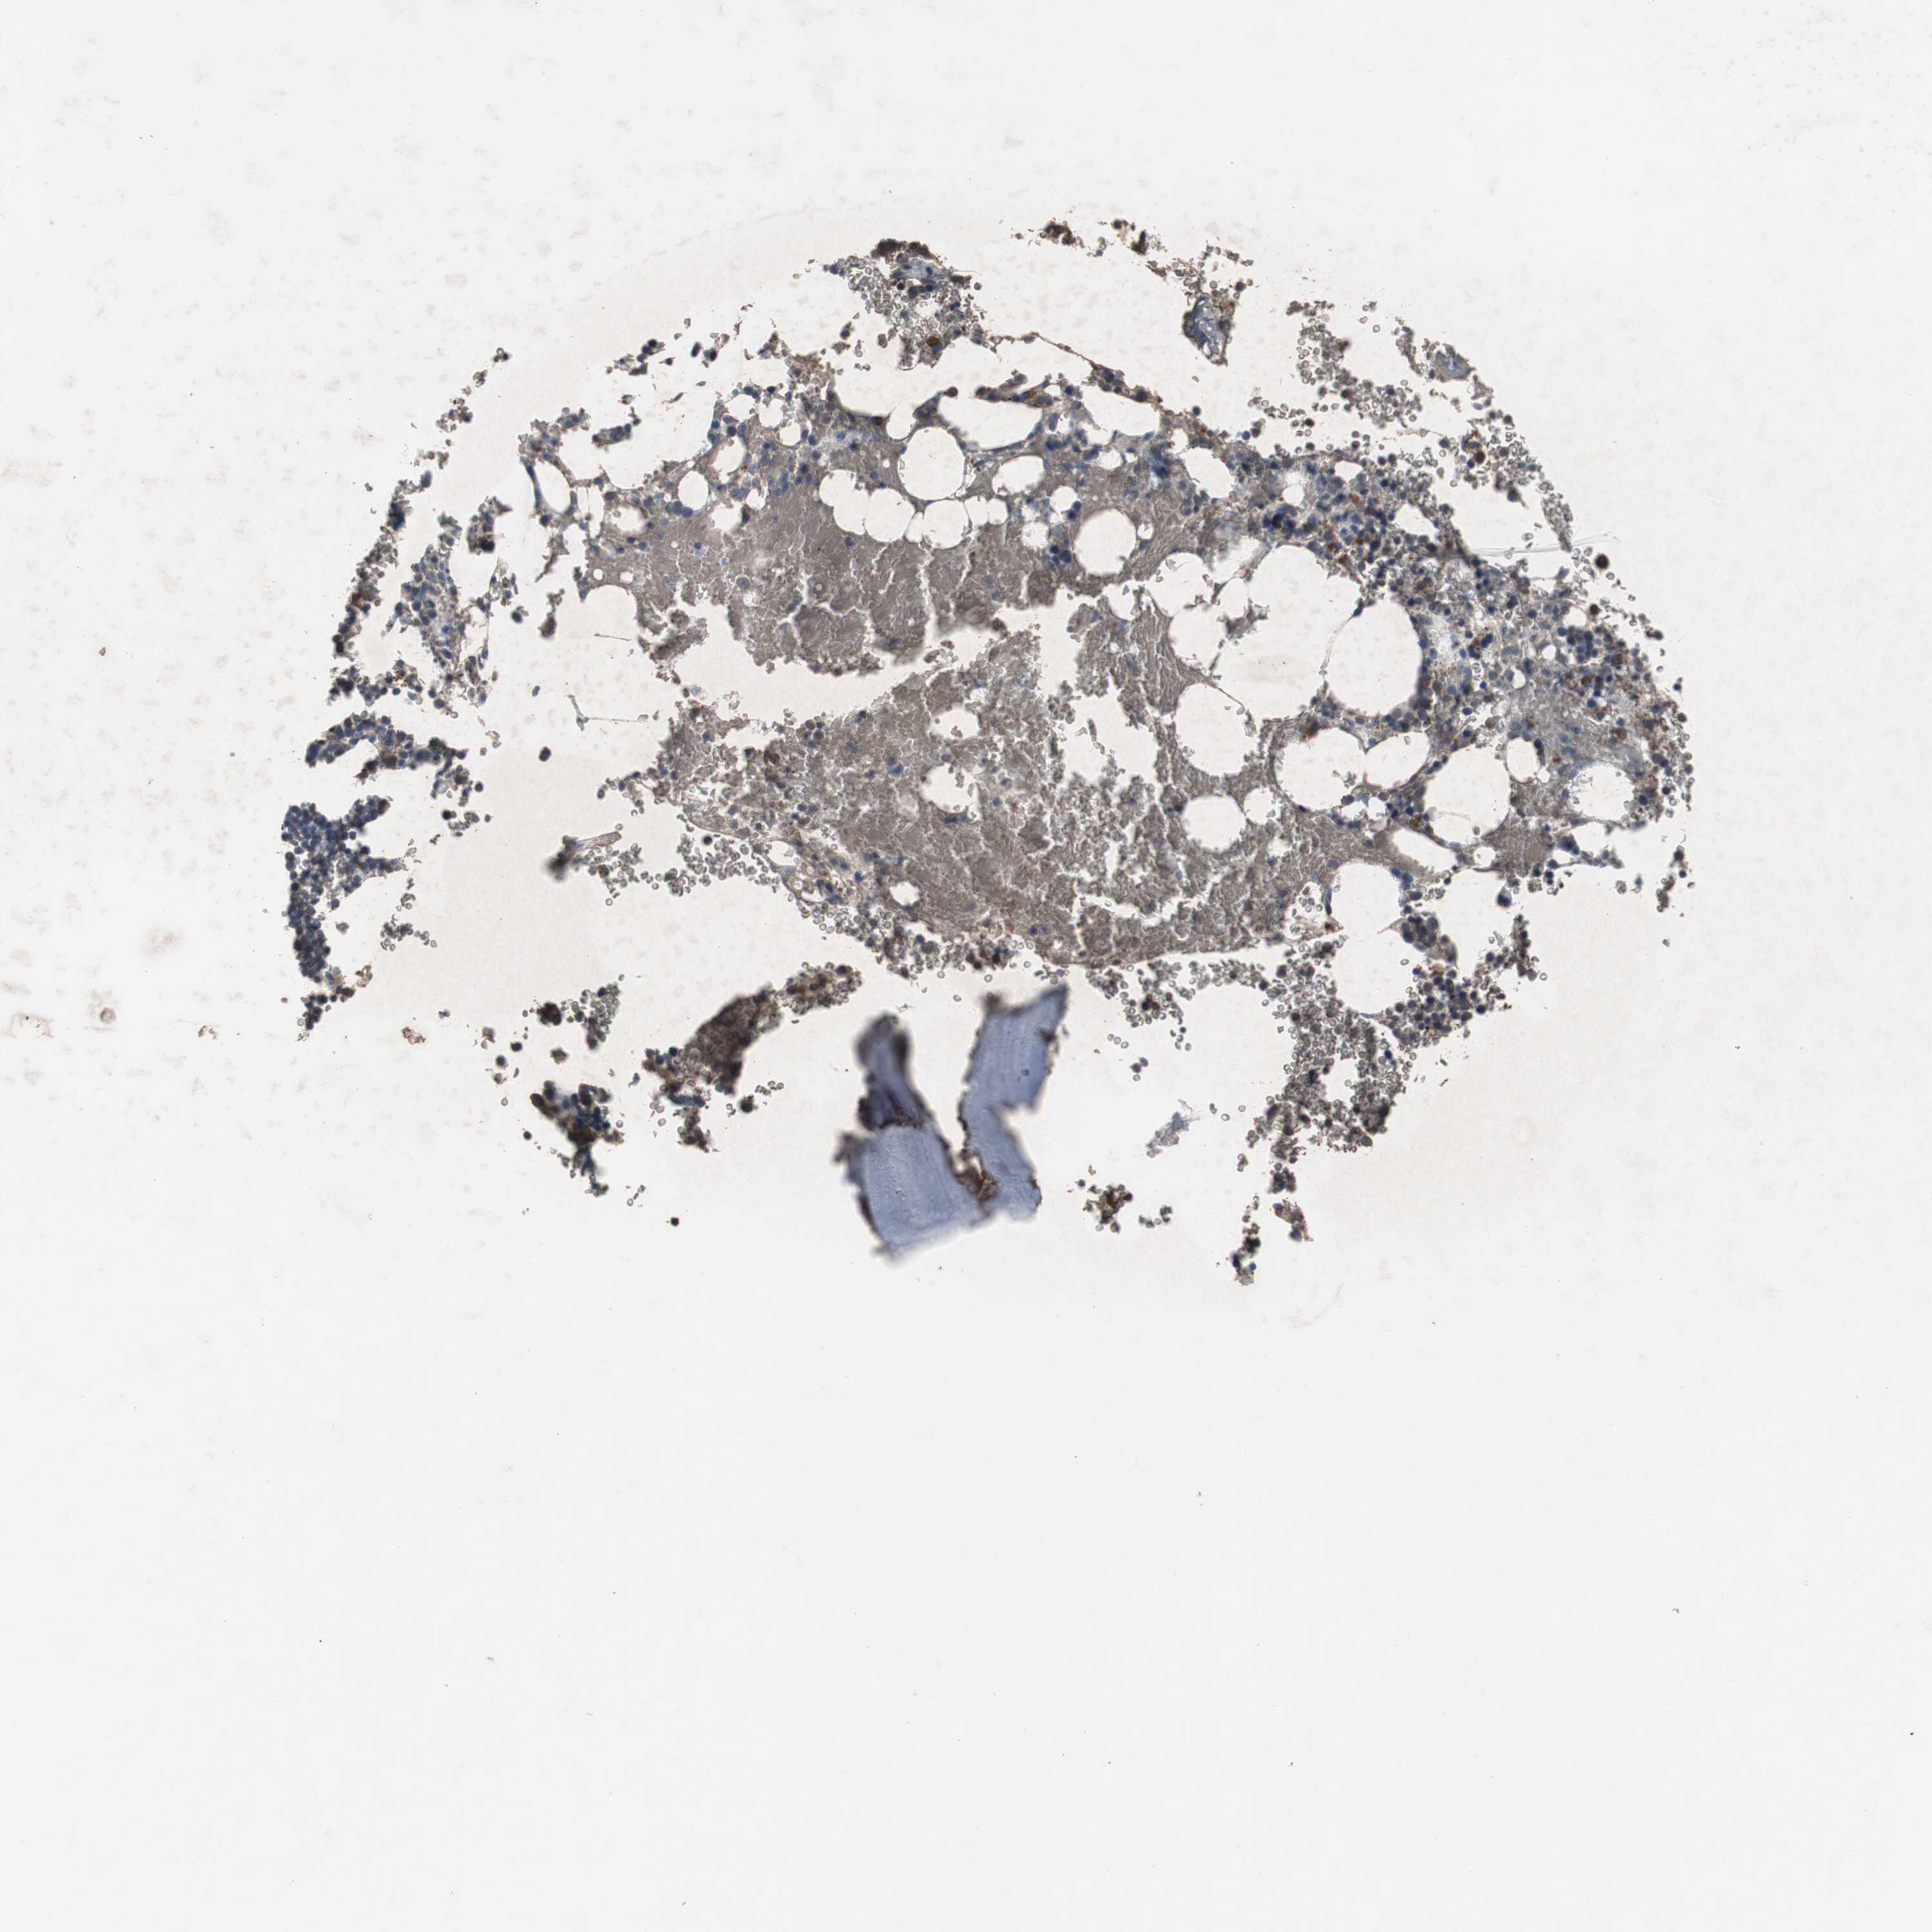

BONE MARROW - Antibody stainingi

Antibody staining in the annotated cell types in the current human tissue is reported as not detected, low, medium, or high, based on conventional immunohistochemistry profiling in selected tissues. This score is based on the combination of the staining intensity and fraction of stained cells.

Each image is clickable and will lead to virtual microscopy that enables deeper exploration of all samples and also displays staining intensity scores, fraction scores and subcellular localization as well as patient and tissue information for each sample.

Antibody HPA007305Antibody HPA007306Antibody CAB000106

Hematopoietic cells LowLowNot detected